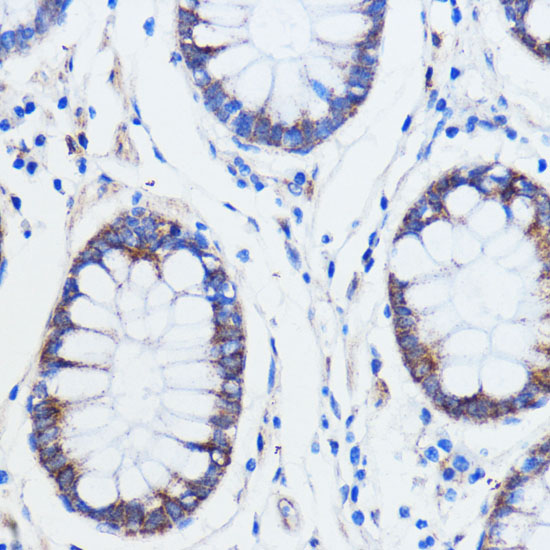

Immunohistochemistry of paraffin-embedded human colon carcinoma using TRIM16 at dilution of 1:100 (40x lens).